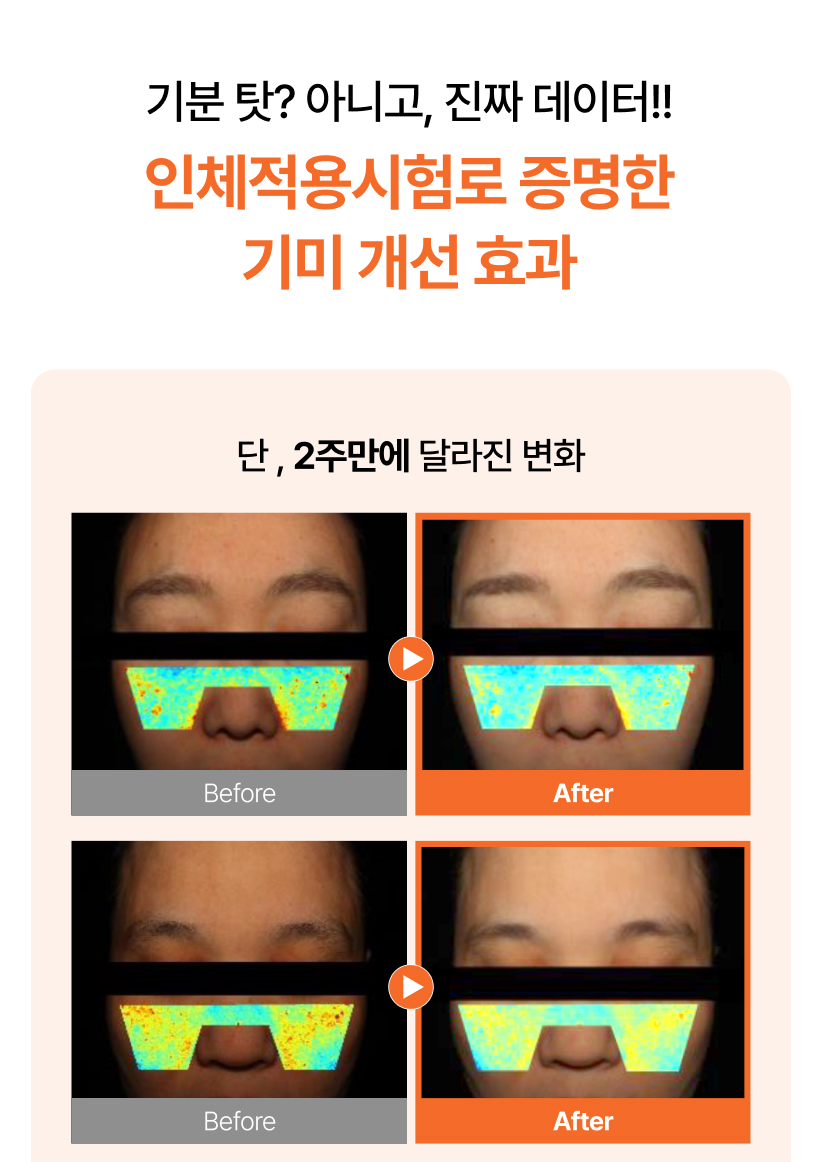

(1+1) 맥퀸뉴욕 다크스팟제로 기미크림 대용량 100g/ 잡티 미백 트라넥삼산 PDRN/ 색소침착 114.53%개선